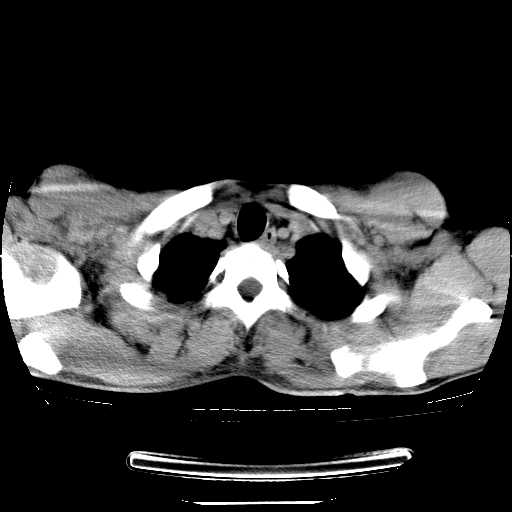

以下是引用dyqct在2008-4-29 8:43:00的发言:[br][br] 支持右侧胸腔包裹性积血。闭式引流管是不是插的太深了?

以下是引用zjzjr在2008-4-29 14:11:00的发言:[br]支持右侧胸腔包裹性积血。闭式引流管是不是插的太深了?胸腔引流,引流管快进入纵隔了.